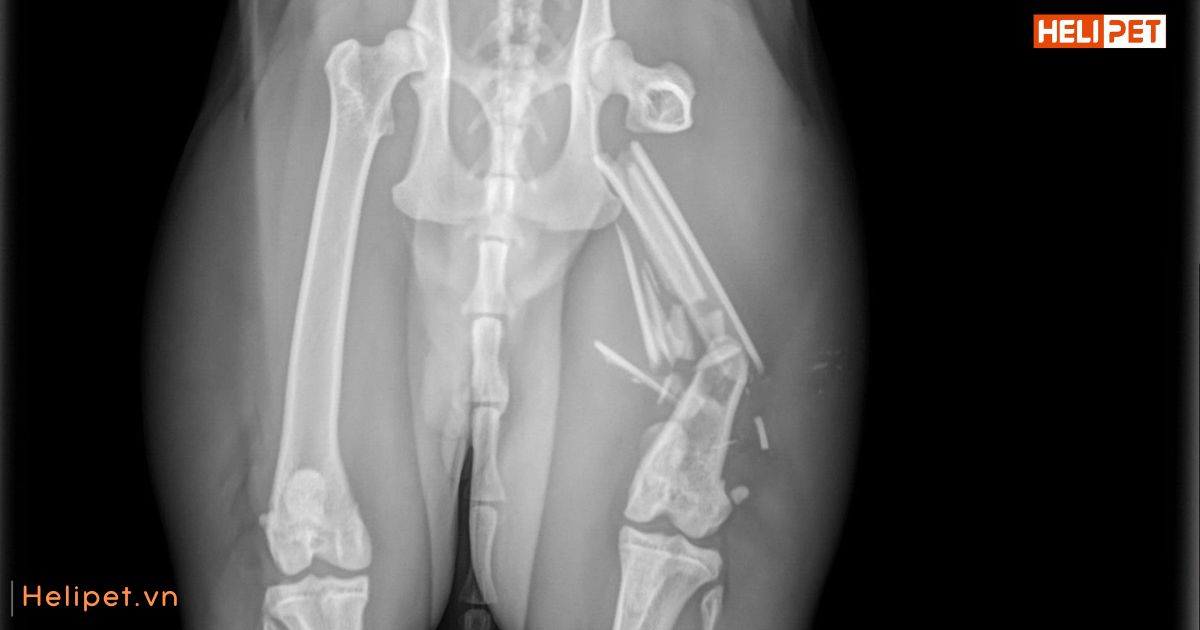

Hình ảnh X-quang một chú mèo bị gãy xương chân

Sau khi thực hiện sơ cứu ban đầu, bạn cần nhanh chóng đưa mèo đến gặp bác sĩ thú y để được thăm khám để chẩn đoán, xác định mức độ nghiêm trọng của vết gãy và quyết định phương pháp điều trị. Nếu xương bị lệch, bác sĩ sẽ phải tiến hành nắn lại, bó bột xương hoặc phẫu thuật để cố định lại xương.

Ngoài ra, bác sĩ có thể sẽ tiến hành chụp X-quang để kiểm tra tình trạng gãy xương và xem xét có tổn thương nội tạng nào xuất hiện không.